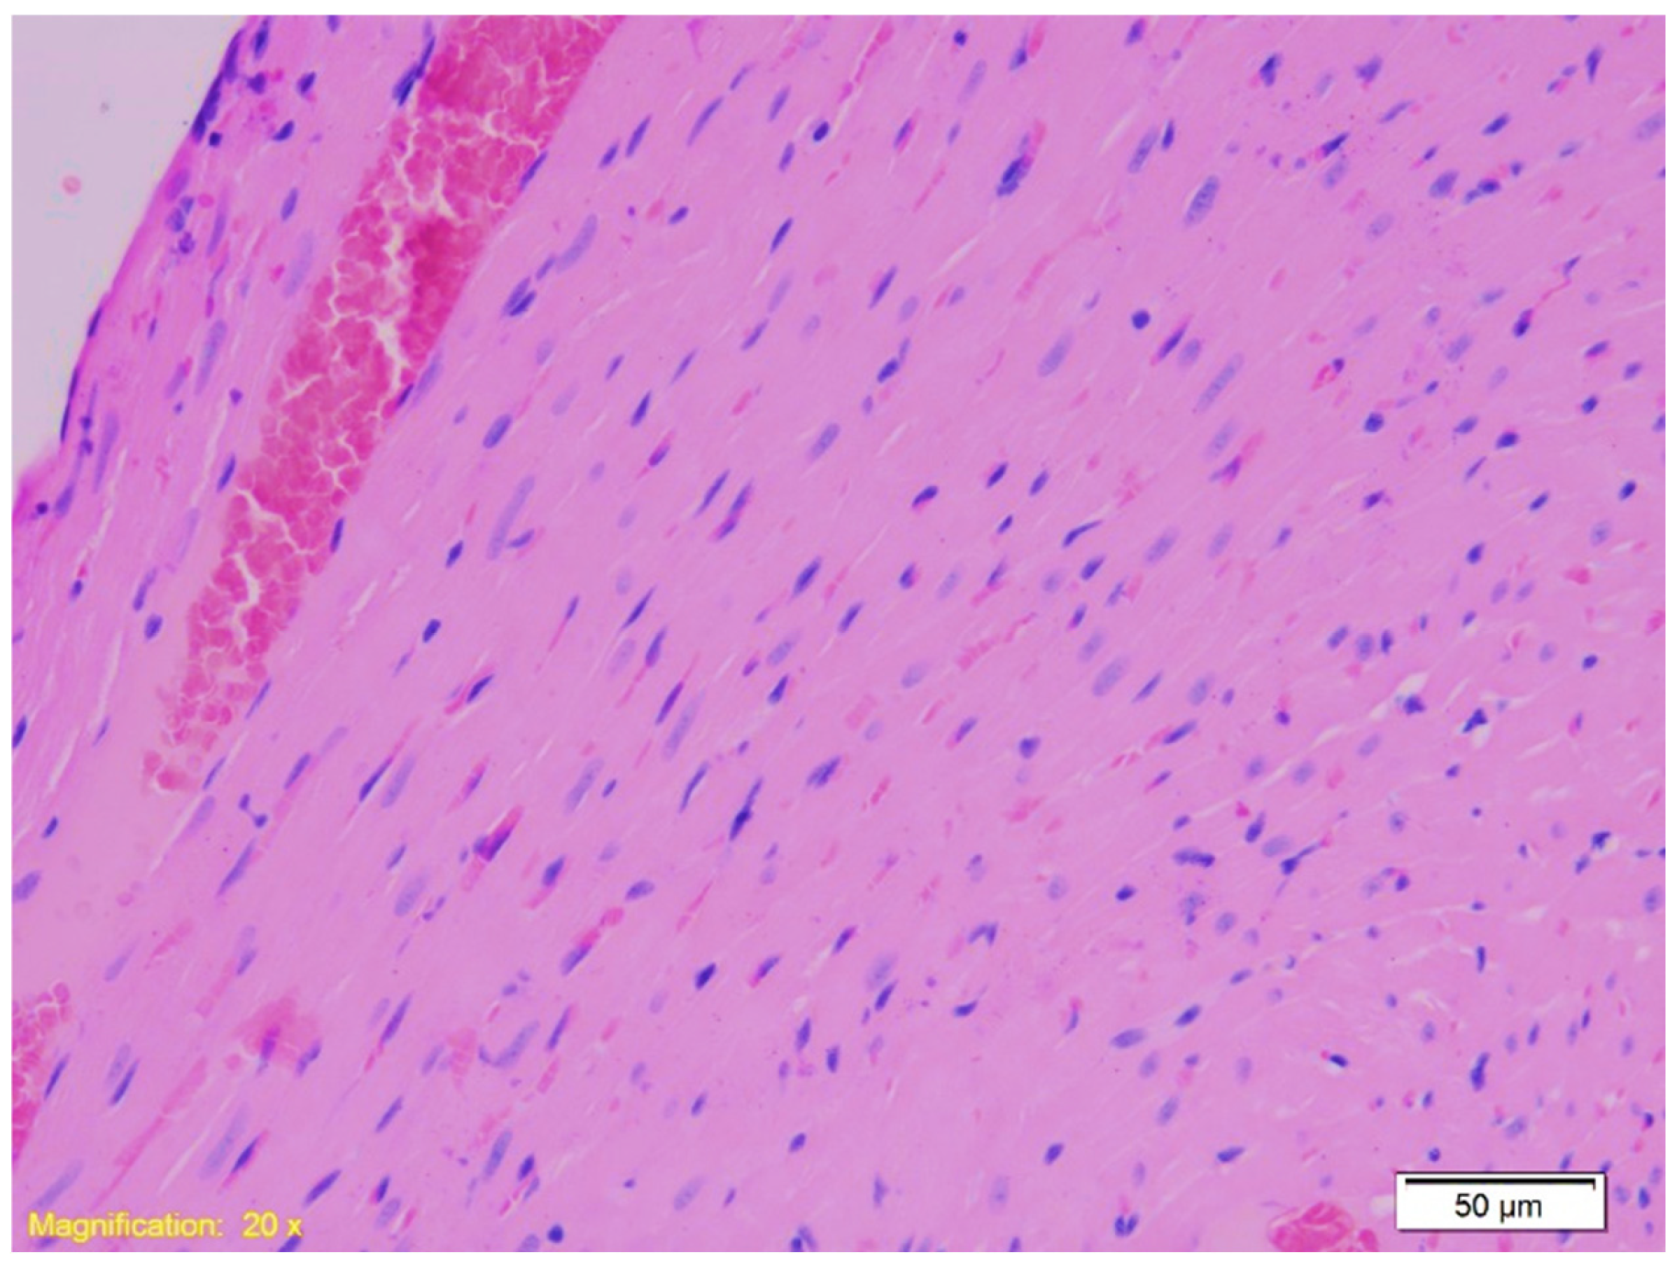

| Heart | Congestion and erythrocyte extravasation in interstitium. | Similar to Group K, with some cardiomyocytes showing finely granular cytoplasm and vacuolar degeneration, suggesting protein denaturation. | Similar to Group K with occasional vacuolar degeneration and protein denaturation in cardiomyocytes. |